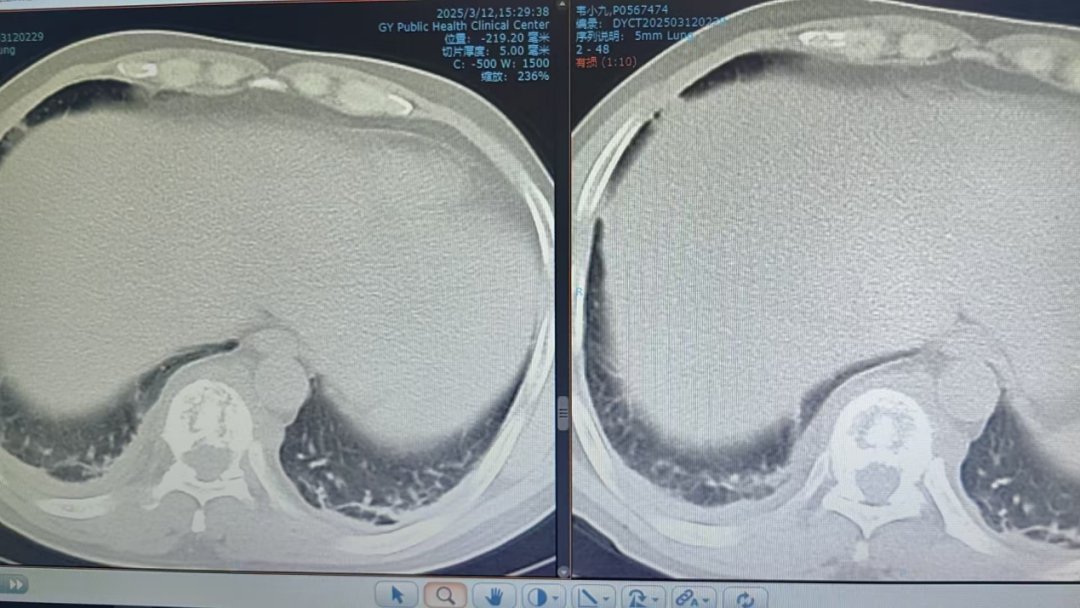

以為是干活勞累,卻突發(fā)癱瘓 “我以為是最近做活路太累了,導(dǎo)致的腰酸背痛,哪曉得突然就癱了!真的感謝周醫(yī)生他們的幫助,把我救回來(lái)了!”談起這番經(jīng)歷,張先生仍心有余悸。 據(jù)悉,今年三月初,42歲的張先生(化名)因胸背疼痛一個(gè)月未進(jìn)行相關(guān)治療,伴隨疼痛進(jìn)行性加重后,入院前3天出現(xiàn)雙下肢無(wú)力、不能行走、大小便失禁等情況。入院時(shí),體查其雙下肢肌力為0,自肋弓以下喪失知覺(jué),無(wú)法坐立,且影像學(xué)檢查顯示,其胸椎上段被結(jié)核性膿腫及壞死骨嚴(yán)重壓迫,脊髓持續(xù)受損。 "每耽誤一分鐘,神經(jīng)壞死風(fēng)險(xiǎn)就增加一分?;颊吣茉僬酒饋?lái)的可能也就減少一分,對(duì)患者家庭是災(zāi)難性后果,我們必須為他爭(zhēng)取時(shí)間。"貴陽(yáng)市公共衛(wèi)生救治中心外三科副主任周波告訴記者;通常情況下,脊柱結(jié)核手術(shù)需2-3周抗結(jié)核治療后再行手術(shù)。但面對(duì)張先生不斷惡化的脊髓損傷,他們必須與患者一同與時(shí)間賽跑:打破常規(guī)的急診手術(shù)決策,進(jìn)過(guò)迅速且嚴(yán)謹(jǐn)?shù)臅?huì)診決策后,靜脈給予一次抗癆治療,團(tuán)隊(duì)當(dāng)機(jī)立斷采用"脊柱前后路聯(lián)合"急診手術(shù)為張先生進(jìn)行施救。“我們首先從前路開胸,清除椎體前方膿腫及壞死組織,植入鈦網(wǎng)替代部分椎體功能,由于椎體跳躍性骨質(zhì)破壞,前路固定不牢固,立即行后路手術(shù),通過(guò)椎弓根釘棒系統(tǒng)實(shí)現(xiàn)脊柱三維穩(wěn)定,再次行后路減壓,雙路徑手術(shù)一次性徹底清除病灶,減壓更充分,復(fù)發(fā)幾率更小。 患者術(shù)前X片 患者胸部CT 患者胸椎核磁共振 術(shù)后復(fù)查的X線 該患者在術(shù)后第一天身體感知覺(jué)有較明顯恢復(fù),第5天開始腳趾恢復(fù)活動(dòng),兩周時(shí)肌力恢復(fù)至3級(jí)以上,截至昨日記者在現(xiàn)場(chǎng)目睹,雙腿已經(jīng)可以自主抬放。周波副主任表示,急性脊髓損傷的黃金救治窗口極短,聯(lián)合入路既能快速減壓又確保長(zhǎng)期穩(wěn)定性,這是恢復(fù)超預(yù)期的關(guān)鍵。預(yù)計(jì)一個(gè)月左右,這位患者就能重新自主行走了。 本次手術(shù)團(tuán)隊(duì)的幾位醫(yī)生正在叮囑患者出院后的注意事項(xiàng) 左起:羅善鵬,石頭,周波,左樂(lè) 專家提示: 腰痛≠腰椎勞損 這些信號(hào)要警惕 針對(duì)近年多發(fā)的"腰痛誤診"現(xiàn)象,周主任特別提醒:腰椎結(jié)核多以持續(xù)性腰痛為主,多伴低熱、盜汗、體重下降等結(jié)核中毒癥狀;而腰椎間盤突出典型表現(xiàn)為腿痛腿麻等。一定要注意的是當(dāng)出現(xiàn)腰痛合并下肢無(wú)力、大小便功能障礙時(shí),無(wú)論屬于哪一種情況都需立即就醫(yī)。 據(jù)統(tǒng)計(jì),我國(guó)結(jié)核感染人群超2億,其中5%-10%的肺外結(jié)核可累及脊柱。專家強(qiáng)調(diào),骨結(jié)核雖發(fā)病率低,但致殘率高,早期規(guī)范治療可避免災(zāi)難性后果。 專家簡(jiǎn)介 周波,男,43歲,副主任醫(yī)師,中國(guó)抗癆協(xié)會(huì)結(jié)核病健康促進(jìn)分會(huì)委員,中華醫(yī)學(xué)會(huì)貴陽(yáng)市骨科分會(huì)委員、貴陽(yáng)市康復(fù)醫(yī)學(xué)會(huì)委員,貴陽(yáng)市骨科質(zhì)量委員會(huì)委員,貴陽(yáng)市艾滋病性病防治協(xié)會(huì)委員,中國(guó)中醫(yī)藥信息學(xué)會(huì)骨科分會(huì)委員,從事臨床醫(yī)學(xué)骨外科專業(yè)15余年,擅長(zhǎng)脊柱結(jié)核及其截癱患者的治療,搶救脊髓功能,擅長(zhǎng)骨與關(guān)節(jié)結(jié)核的診治,髖、膝關(guān)節(jié)置換的治療,術(shù)后療效顯著,有效減少患者的致殘率。在國(guó)內(nèi)學(xué)術(shù)核心雜志發(fā)表學(xué)術(shù)專業(yè)文章15篇。